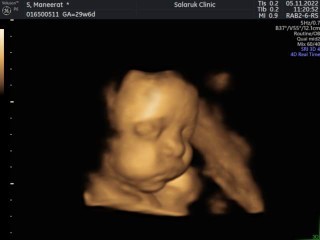

แชร์ภาพอัลตร้าซาวด์4D

วันนี้มาซาวด์ค่ะ ท้อง28สัปดาห์ เจอลูกชายแทะตีนๆ ขำพรืดเลยค่ะ😂 ท่าทางอร่อยมาก แม่ๆท่านไหนมีรูปซาวด์ฮาๆมาแชร์กันมั๊ยคะ❤️

หนูลู๊กกก ฟีลจะซึ้งๆคิดถึงลูก สรุปขำแทน 🤣 ตื่นเต้นตามเลยค่ะ บ้านนี้เดือนหน้าถึงได้เจออีกรอบตอน 28 เพื่อดูว่ารกเลื่อนขึ้นมั้ย เห็นน้องแล้วอยากข้ามไปเดือนหน้าเลยค่ะ 🥺

มือไม่โชว์ โชว์เท้าไปเลยค่ะ